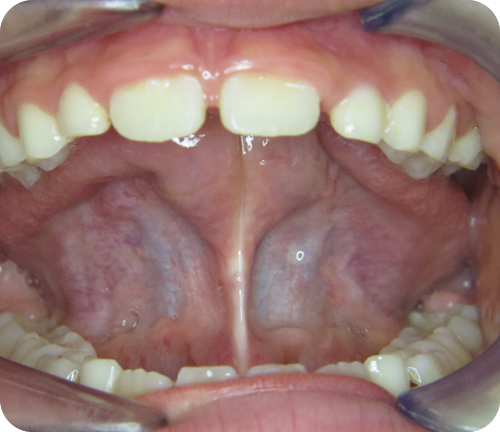

Bei Säuglingen lässt sich das Zungenband mit Hilfe eines Lipers passiv dehnen.